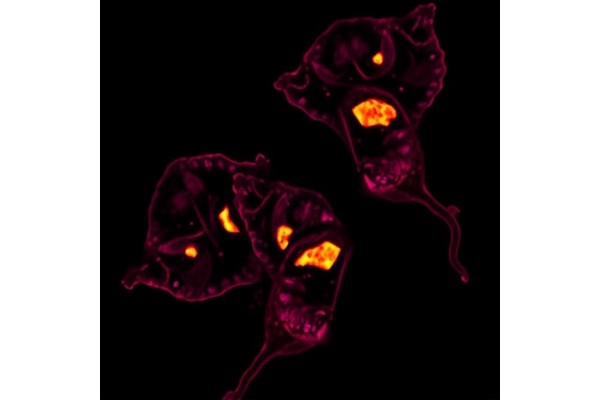

Home Science News Biology New Study Reveals Striking Parallels Between Atherosclerosis and Tumor Development June 17, 2025 in Biology Reading Time: 4 mins read 0 67 SHARES 606 VIEWS Share on